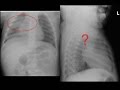

RSV Bronchiolitis Subpleural Consolidation on Mindray TE-X linear array transducer lung preset

6 m.o. Boy RR 40s, subcostal retractions with head bobbing, RSV pcr positive. Lung US using Mindray TE-X linear array transducer detects subpleural consolidation.